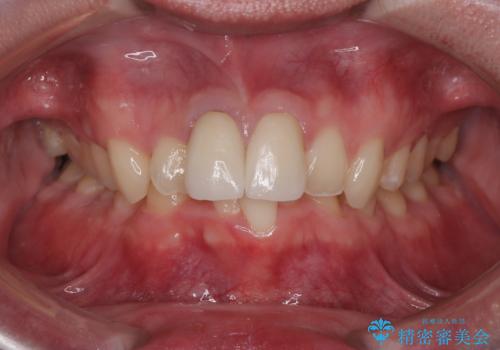

噛み合わせを改善するための矯正治療をご提案しましたが、患者様のご希望により矯正治療と根管治療の再治療は行わず、ファイバーコア(土台)+オールセラミッククラウンによる補綴治療を選択しました。

審美性と強度を両立させるため、透明感のあるオールセラミッククラウンを採用し、周囲の天然歯に自然に調和するよう色調・形態を調整しました。